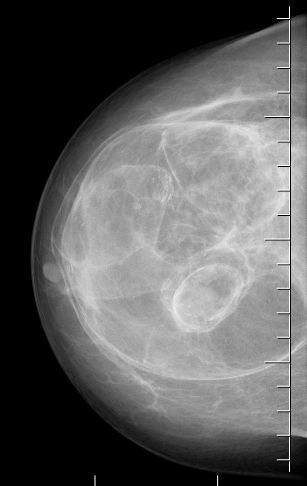

При маммографии гамартома выглядит как округлое или овальное образование, окружённое тонкой капсулой с чёткими ровными контурами. Для неё характерно смешанное строение, которое напоминает срез салями: участки более плотной железисто-фиброзной ткани чередуются с жировой. При этом гамартома обычно не содержит отложений кальция [8].

Маммография